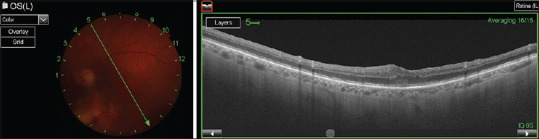

Foveal adhesion of a dexamethasone implant: Evaluation and follow-up via multimodal imaging.